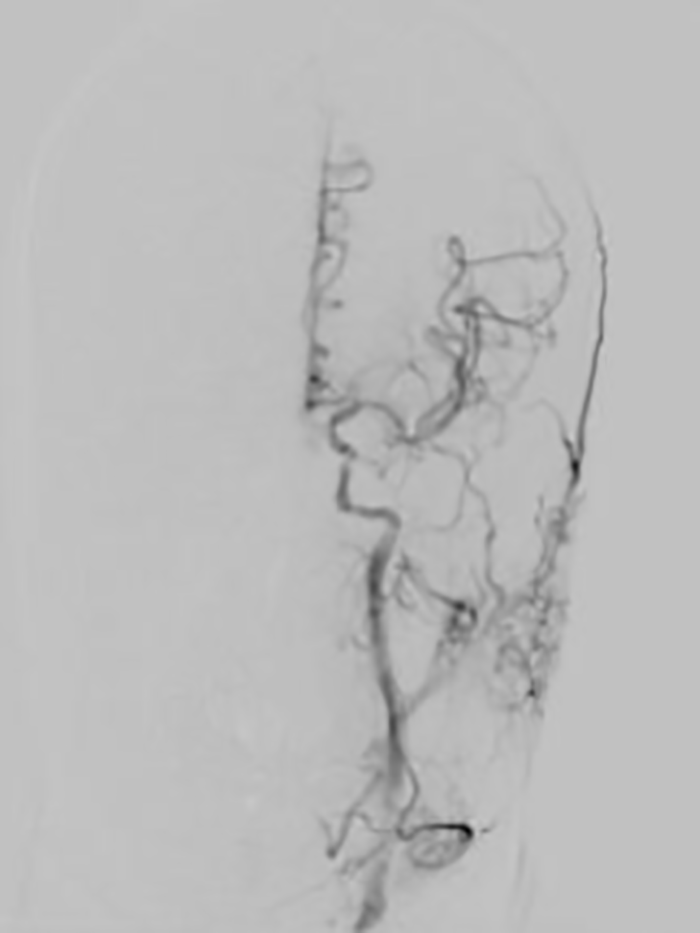

▲患者术后脑血管完全再通

次日患者神志转清,四肢活动自如,家属见状非常激动,对卒中团队迅速高效的“脑卒中绿色生命通道”以及精准的判断和救治能力竖起了大拇指!

▲患者次日神志及肢体肌力逐渐恢复